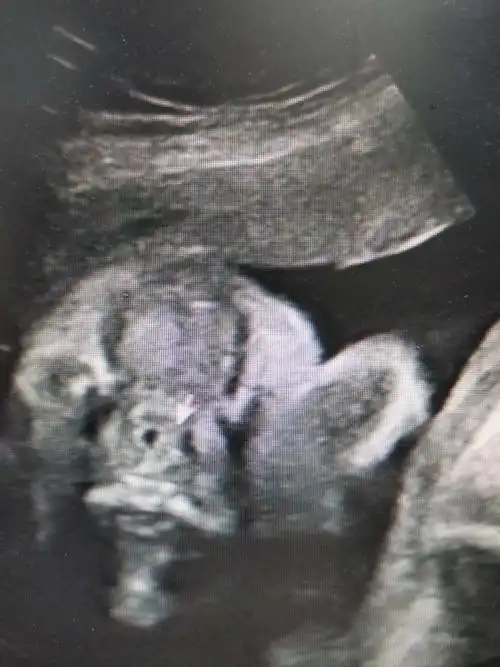

超声诊断胎儿唇腭裂